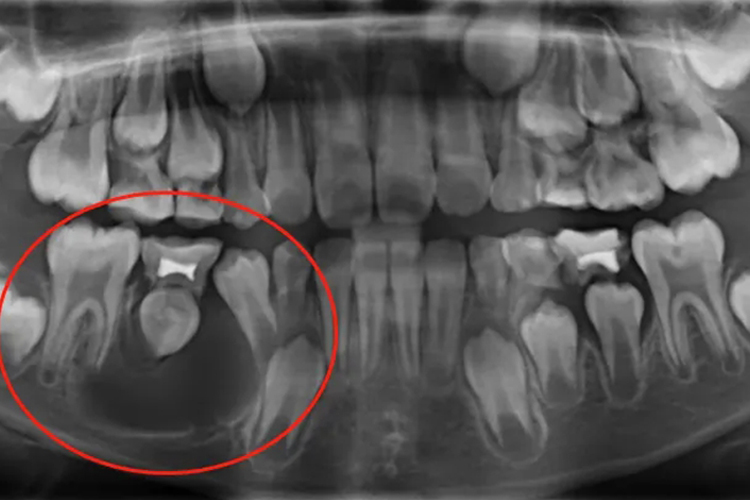

颌骨囊肿的症状可表现为囊肿在骨内呈膨胀性、缓慢生长。早期无任何症状,很多在常规X线检查时发现。囊肿逐渐发展而压迫周围骨质使之膨隆并吸收变薄,触诊有乒乓球样感;骨质完全吸收,囊肿突入软组织,软而有弹性并有波动感。囊肿多向口腔前庭膨出致颌骨及面颊部变形。

颌骨囊肿根据其发病原因可分为牙源性及非牙源性两大类。牙源性囊肿最常见,是由成牙组织或牙的上皮或上皮剩余演变而来;非牙源性囊肿则可由胚胎发育过程中残留于颌骨内的上皮发展形成,如面裂囊肿,亦可为损伤所致的血外渗性囊肿以及动脉瘤样骨囊肿等。

颌骨囊肿多采取手术治疗。其中小型囊肿可做根管治疗,充填后做囊肿摘除;大型颌骨囊肿患者因颌骨病变涉及范围较大,术后易导致牙面部畸形,多主张先采用囊肿开窗减压术,缩小病变范围,恢复颌骨外形。

角化囊性瘤容易复发,甚至可发生恶变,因此手术刮除要求更彻底,在刮除囊壁后用苯酚或硝酸银等腐蚀剂涂抹骨创,或加用冷冻疗法,以消灭子囊,减少复发,必要时还可在囊肿外围切除部分骨质。